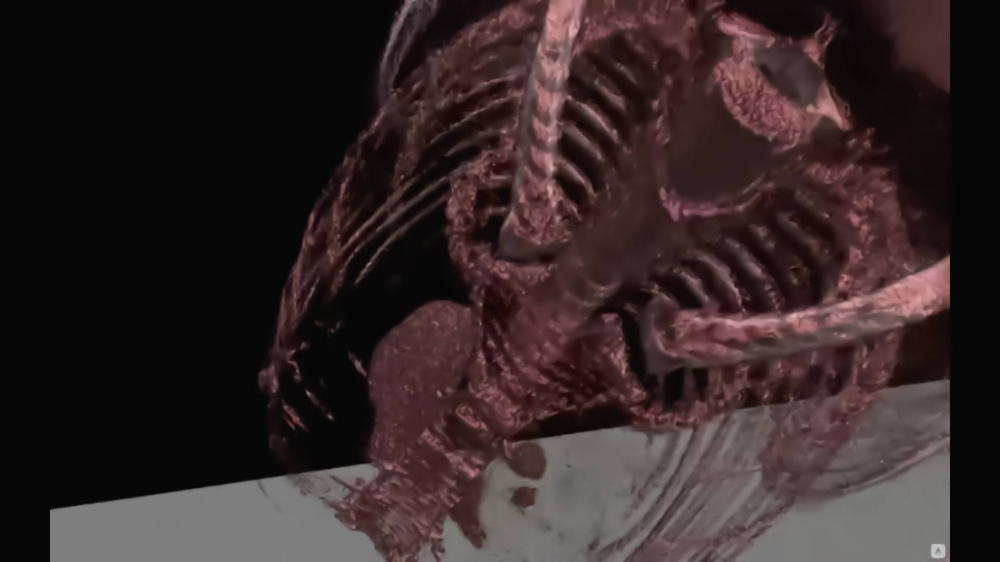

Thanks to our program, you will be able to manage lists of your patients in a quick and organized manner, saving time and more efficiently analyzing images from a computer tomograph or magnetic resonance imaging. The application allows you to load photos into the Virtual Reality environment, giving you the opportunity to view and analyze them in a new, unconventional way. Photos displayed in the form of 3D models can be freely rotated and viewed from different angles.